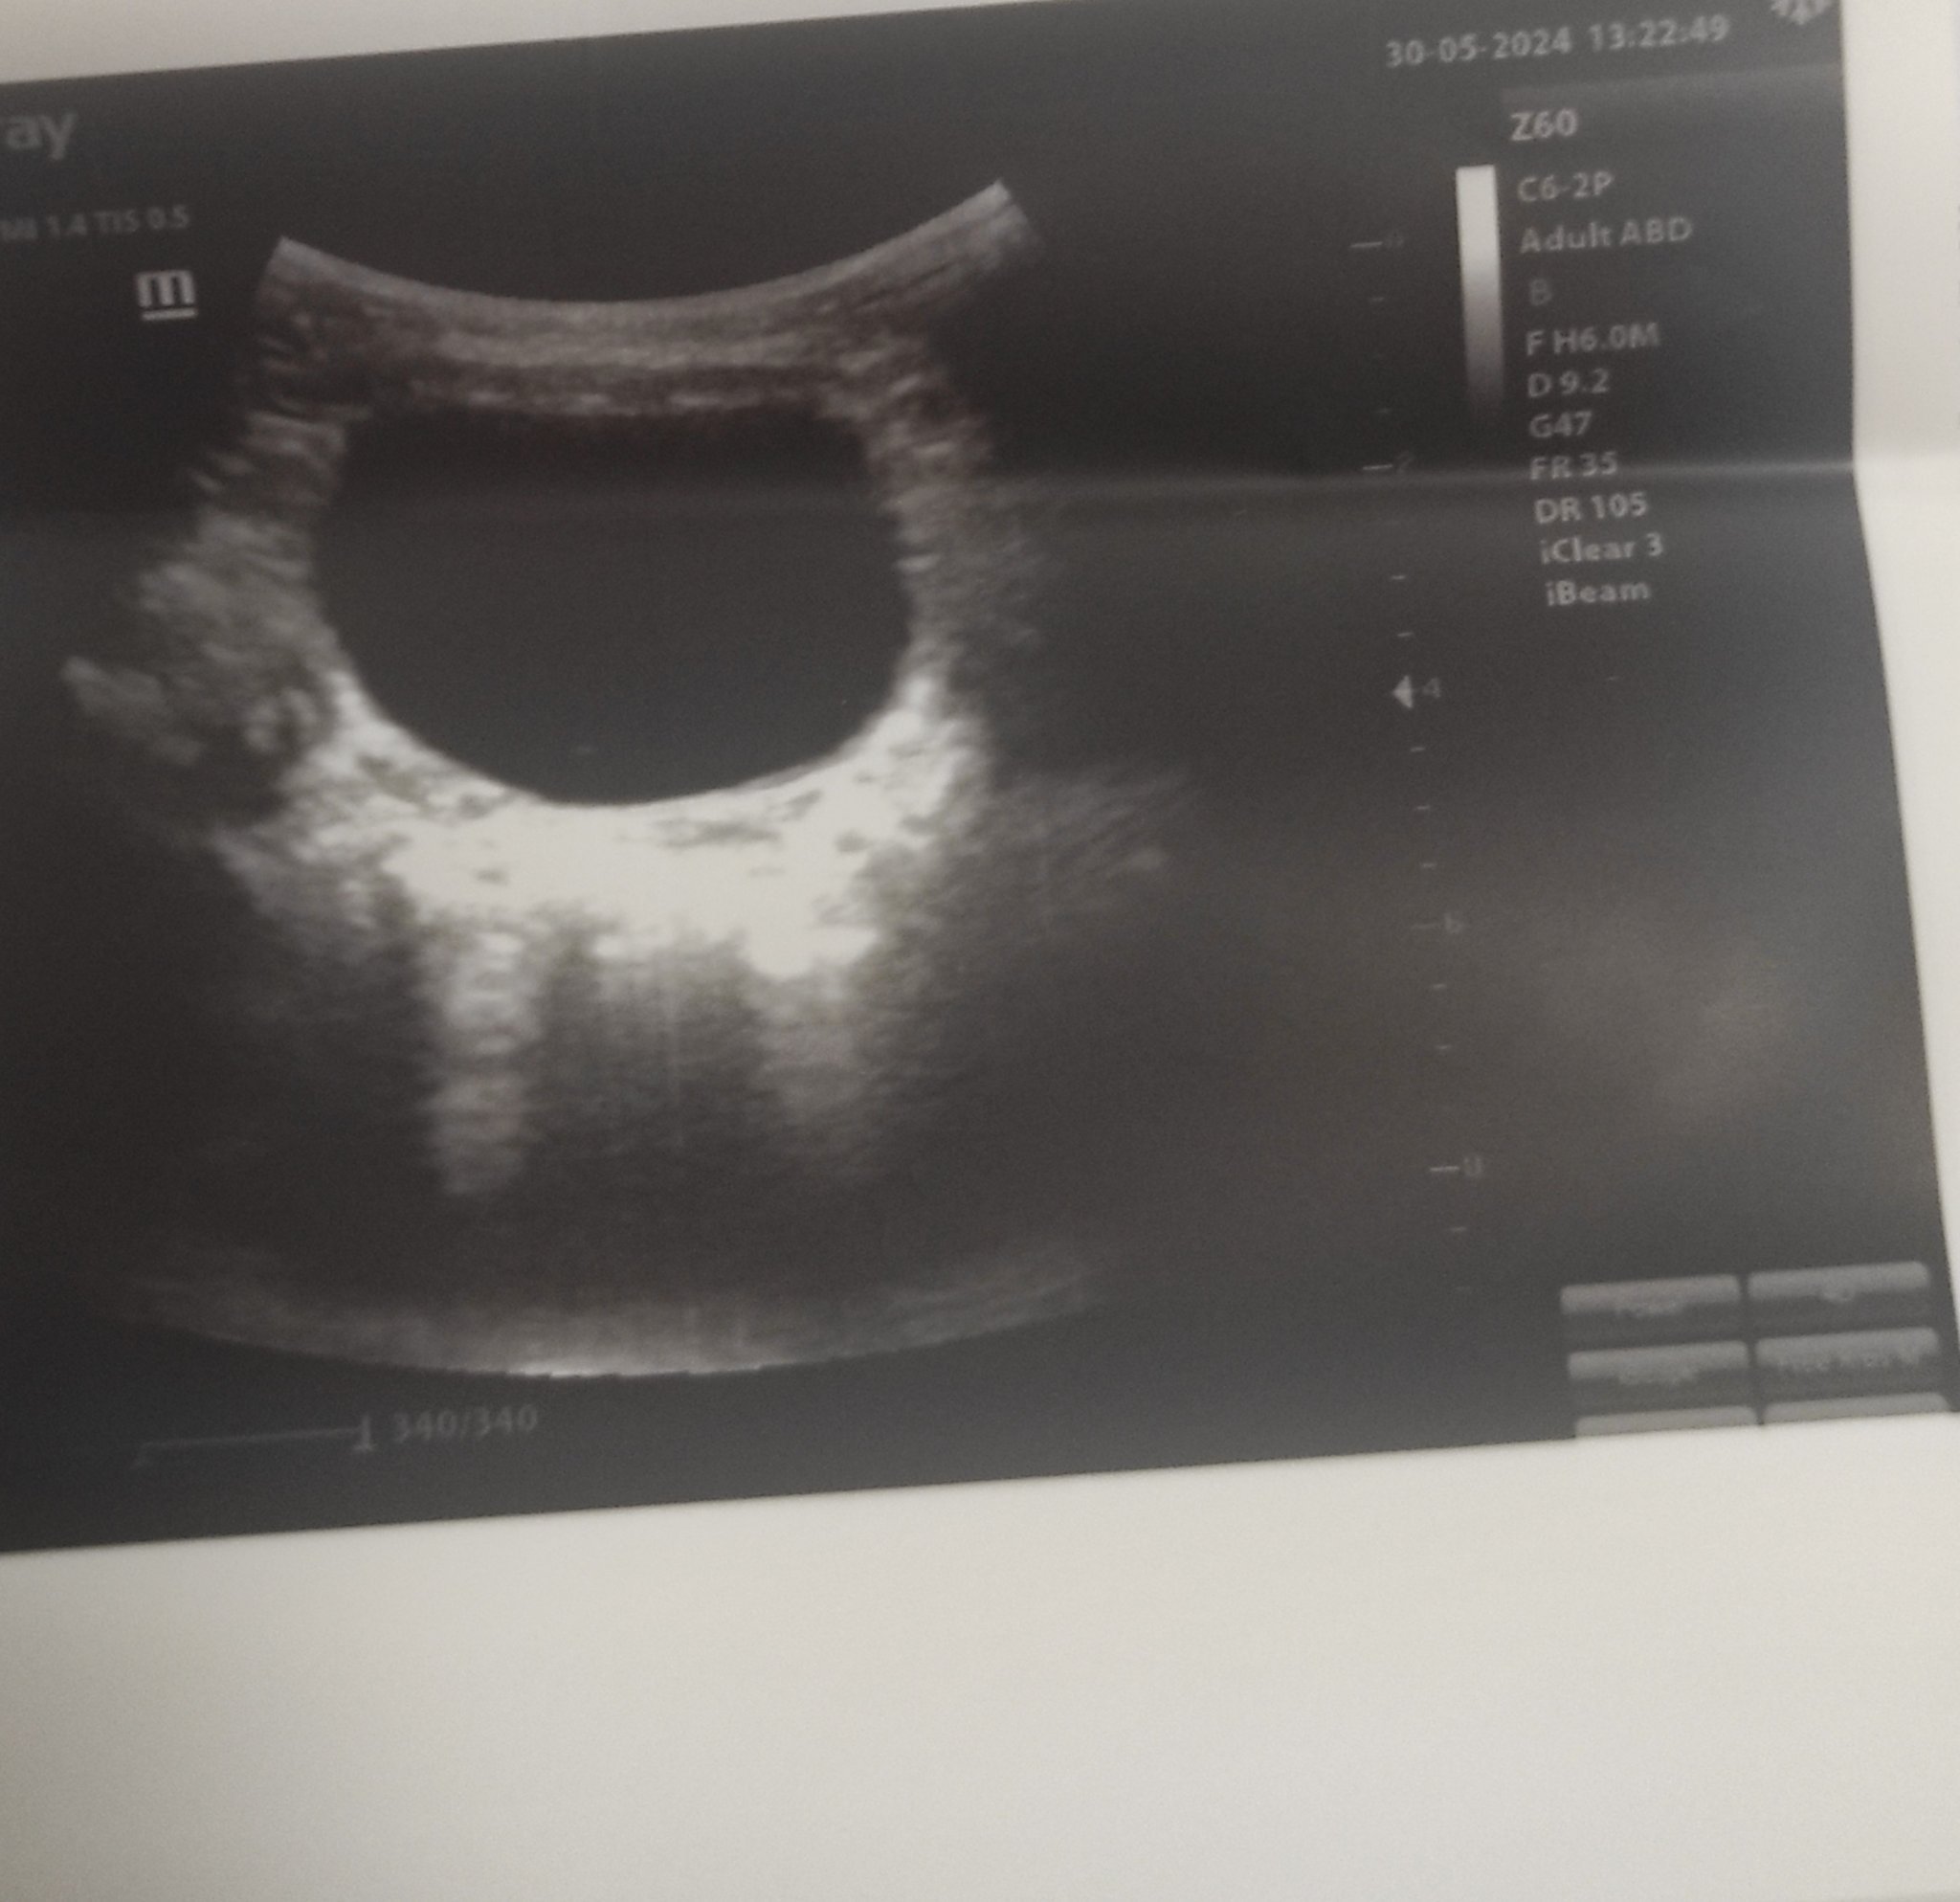

Сега съм се вгледала в снимки .